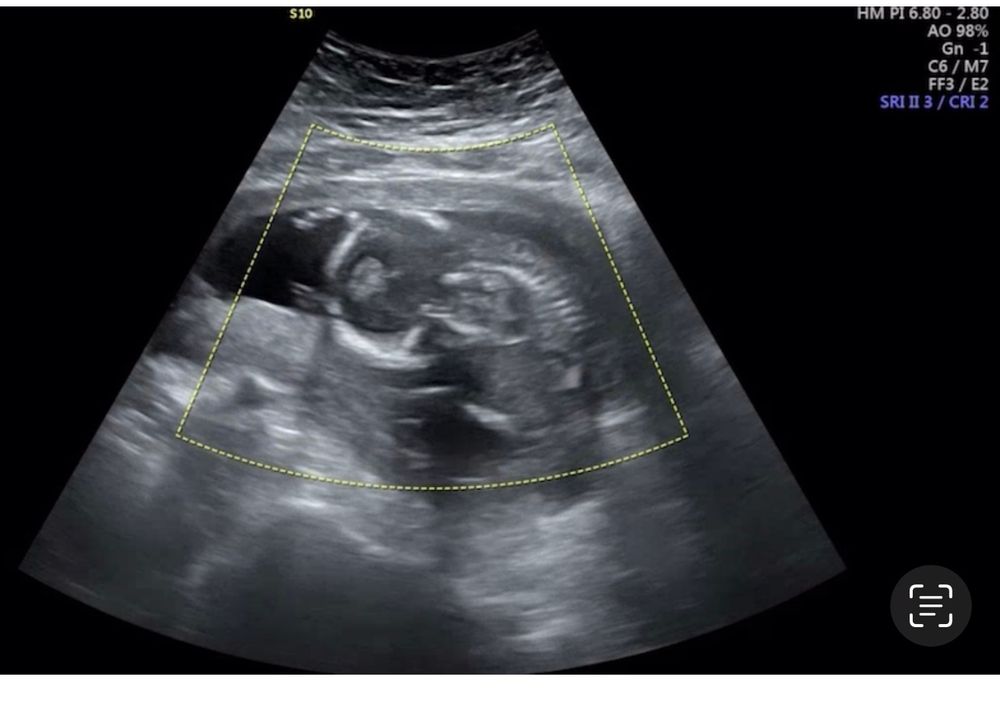

Всем привет . Подскажите может у кого-то так было , вчера были на узи срок 16 недель, по узи врач сказал все отлично . Но мне кажется что наша малышка уж очень странную позу приняла, как будто крючком лежит голову поджала сильно еще и ручками обхватила,на фото надеюсь видно . спросила у доктора он сказал что ей так удобнее поэтому, но я все равно переживаю и нигде не могу найти информацию нормально ли это ? До этого были на узи в 12 недель там лежала ровненько

Они и ноги к ушам могут притянуть , все ок , так и называется положение «поза эмбриона»